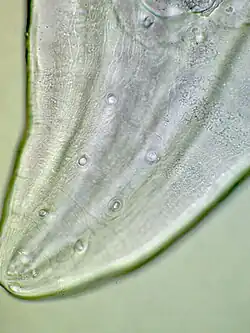

Gang van rondworm in menselijke lip